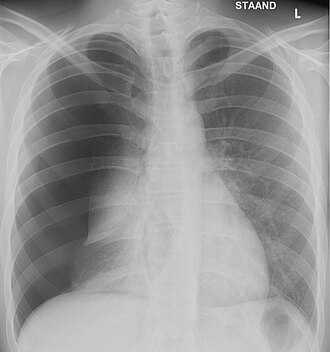

- Pluća [6] (Pneumotoraks)

Barotrauma pluća kod Scuba ronjenja (Scuba Diving) može nastati zbog promjene tlaka u plućima tijekom izranjanja. S izranjanjem se visok tlak plina u plućima smanjuje, zbog smanjenja okolnog tlaka, što uzrokuje širenje plina i porast tlaka u plućima i prsnom košu. Ako se u toj fazi izranjanja ne izjednači tlak, izbacivanjem viška plina, može doći do pucanja plućnog tkiva.

Kad se tlak u plućima poveća, kod ronjenja se javlja bol u prsnom košu koja koji ga upozorava, pravodobno spriječiti nastanak barotraume . Ako tlak zraka u plućima i dalje raste i prijeđe vrijednost od 10-13 kPa (u prosjeku 10,7 kPa u odnosu na vanjski tlak zraka, on neće samo izazvati rupturu zdravog plućnog tkiva već i arterijsku plinsku emboliju, praćenu pojavom zraka u plućnom intersticijalnom prostoru, odnosno u prostoru oko krvnih žila pluća, koji uzrokuje plućni intersticijalni emfizem. Iz ovog prostora plin dalje može prodrijeti u hiluse i mediastinum a otuda u pleuralnu i perikardijalnu šupljina i trbušnu maramice.[3]

Intersticijalni emfizem pritišće male krvne žile pluća izazivajući porast tlaka u plućnim arterijama, što ima za posljedicu izlazak tekućine u intersticijalne prostore i pojavu alveolarnog edema (otoka) što još više pogoršava protok u plućnoj cirkulaciji i pogoduje nastanku hipoksije u organizmu.

Mehanička ventilacija pluća koja se rabi u reanimaciji bolesnika kod raznih vrsta bolesti može dovesti do barotraume pluća. Kako bi se u uređajima osigurala ventilacija ona je povezana s promjenom brzine dovoda plina a samim tim i promjenom tlaka, te u slučaju bilo kakvih propusta u radu može nastati ruptura alveola i pojava pneumotoraksa, plućnog emfizema, prodora zraka u medijastinalni prostor (pleuromediastinum). Tenzijski pneumotoraks u jedinicama intenzivne njege relativno je česta pojava kod bolesnika na mehaničkoj ventilaciji, kao posljedica barotraume. Učestalost pojavljivanja veća je od 25% kod bolesnika na mehaničkoj ventilacija s rizikom rasta kod dužeg trajanja ventilacije. Smrt neposredno izazvana barotraumom pluća javlja se u 13-35% slučajeva.[13]